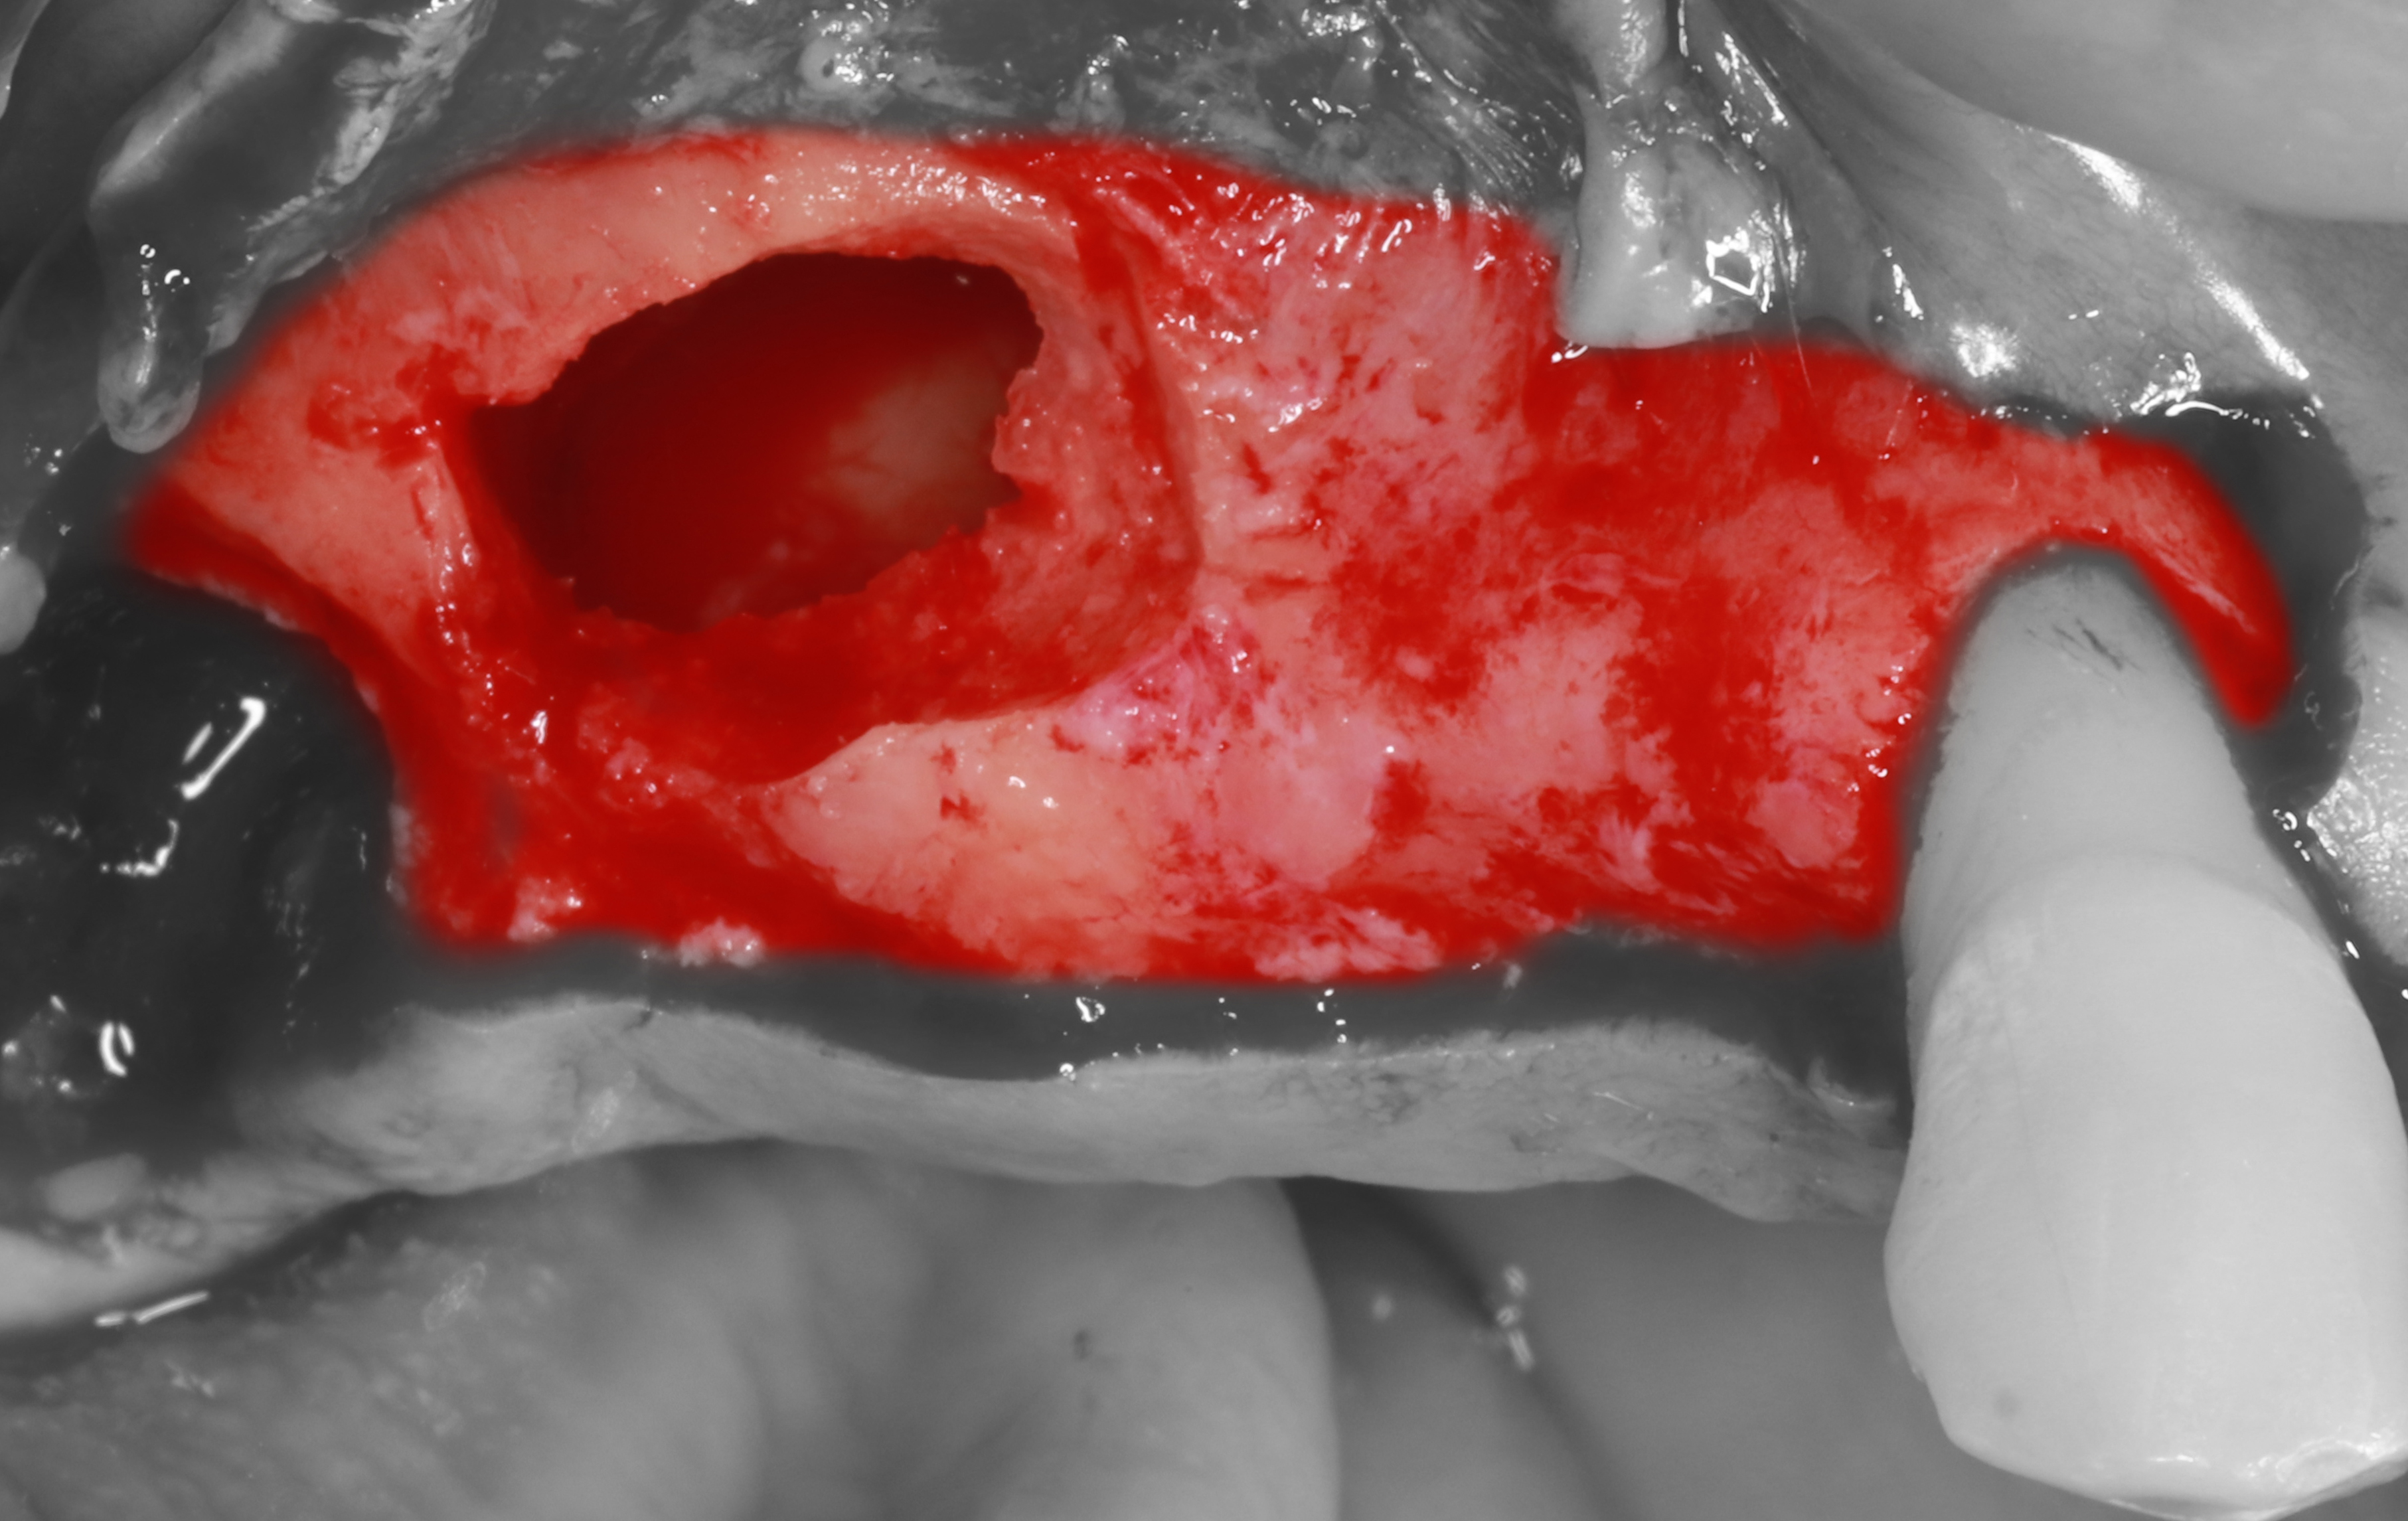

2) Удален зуб 2.8, проведены крестальный, сулькулярный и мезиальный вертикальный разрезы, отслоен СНЛ.

3) С помощью прямого наконечника и алмазной фрезы проведена остеотомия латеральной стенки ВЧ пазухи, с помощью кюрет начато отслаивание Шнайдеровой мембраны.